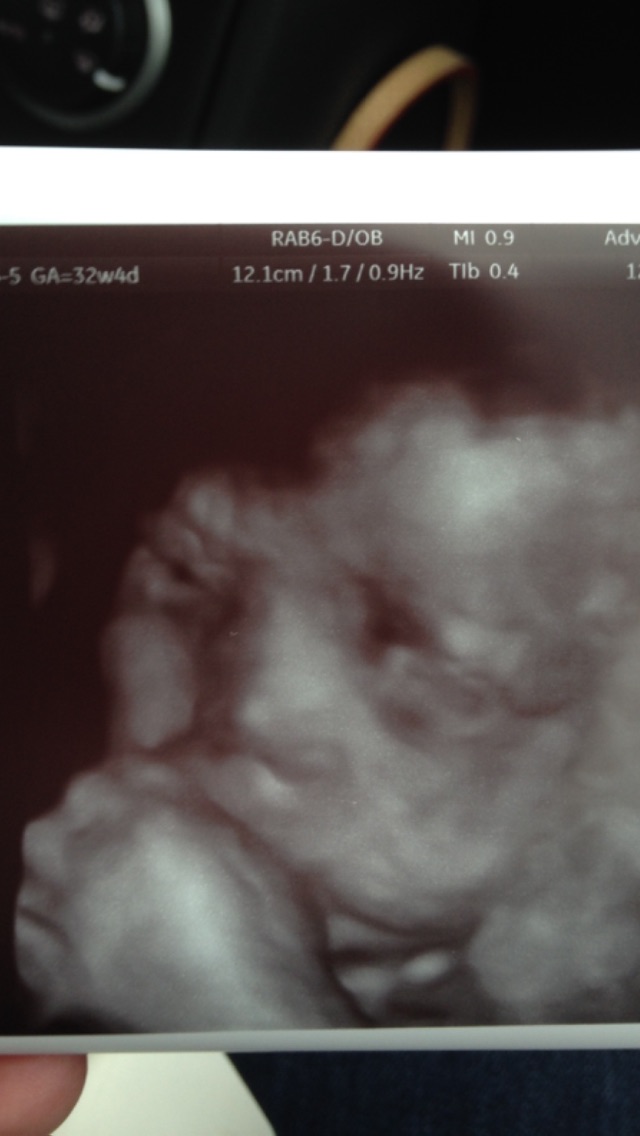

Morning ladies! Had a great weekend! We decorated the ten foot tree that my husband Clark Griswold bought on Friday then Saturday we got to see our little man on 3d and hd live and he cooperated which was awesome and then we went up to Boston for massages and dinner at top of the hub (52 floors up overlooking Boston) followed by a night stay in a hotel and I slept in until....8 a.m. I prob haven't done that since my daughter was born! Amazing